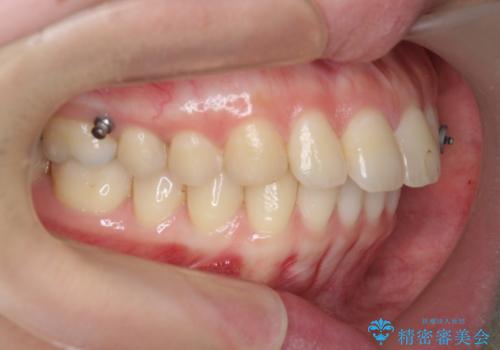

カリエール・マイクロインプラントを用い、時間はかかりましたが大きく歯の後方移動が達成され、前歯の見た目が大きく改善されました。

大きな後方移動を達成するにはマイクロインプラントと日常的なゴムかけが大切です。